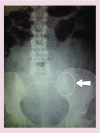

Women with benign heavy menstrual bleeding have the choice of a number of medical treatment options to reduce their blood loss and improve quality of life. The role of the clinician is to provide information to facilitate women in making an appropriate choice. Unfortunately, many options can be associated with hormonal side effects, prevention of fertility and lack of efficacy, leading to discontinuation and progression to surgical interventions. Herein, we discuss the various options currently available to women, including antifibrinolytics, nonsteroidal anti-inflammatory preparations, oral contraceptive pills and oral, injectable and intrauterine progestogens. In addition, we describe the more novel option of selective progesterone receptor modulators and their current benefits and limitations.